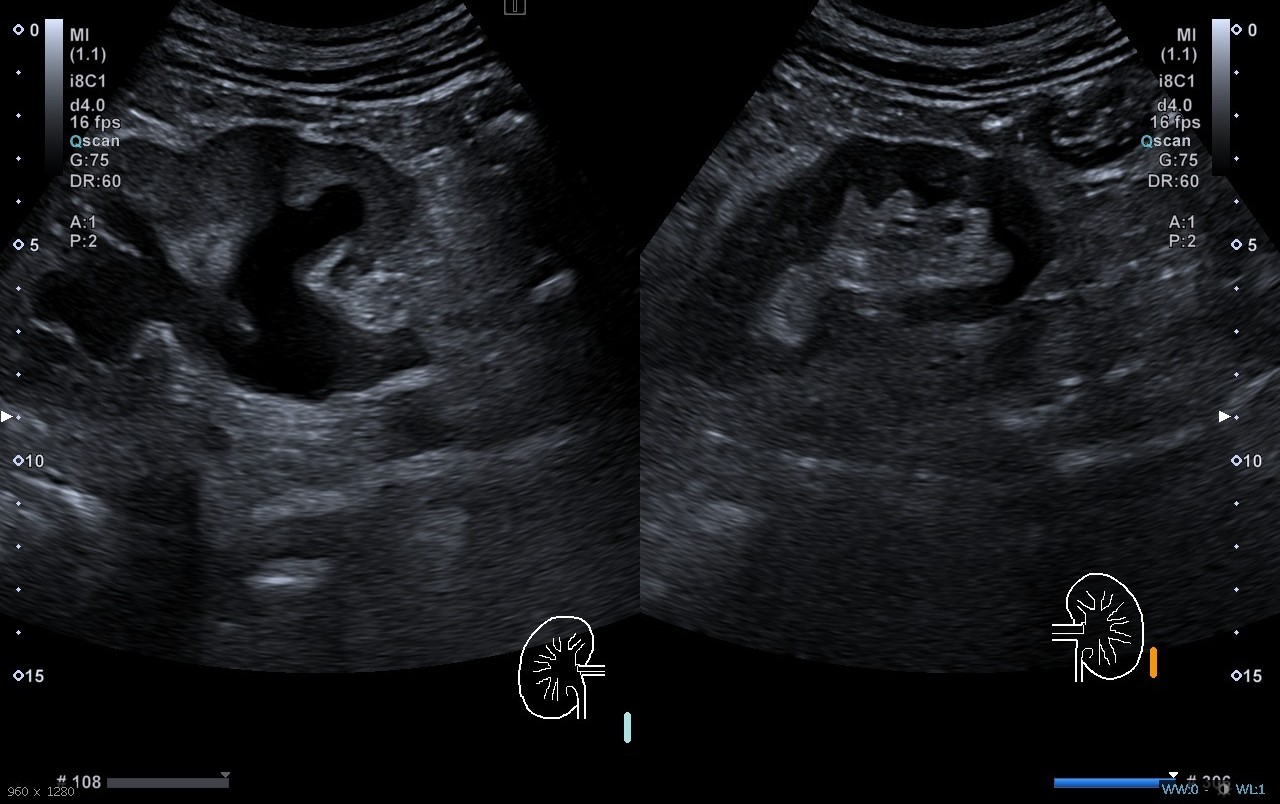

Hombre de 69 años que acude al CS por epigastralgia irradiada hacia hipocondrio izquierdo, náuseas y vómitos de <24 h de evolución. Asocia síndrome miccional y molestias en hipogastrio, hiporexia y coluria, sin fiebre u otra sintomatología. Dada ausencia de mejoría tras analgesia es derivado a Urgencias Hospitalarias. A su llegada dolor persistente y mal estado general. A la exploración física presenta palidez cutánea y deshidratación, abdomen doloroso a la palpación en región epigástrica e hipogástrica e irradiación hacia fosa renal izquierda.

Diagnóstico: Ureterohidronefrosis grado 3. Pancreatitis aguda de origen biliar.

El paciente ingresa en Digestivo por diagnóstico de pancreatitis aguda, con seguimiento simultáneo por Urología. Se realiza CPRE sin incidencias y posteriormente desarrolla una IRA prerrenal secundaria a proceso neoproliferativo renal. Se decide nefrouretectomía radical derecha.